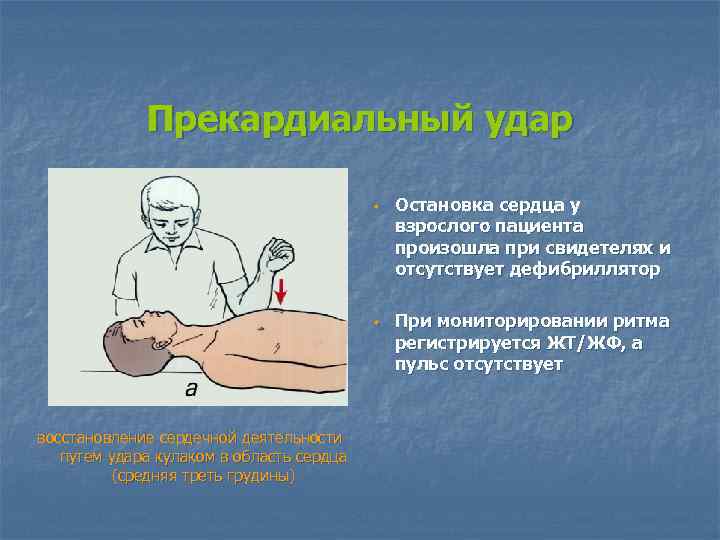

Прекардиальный удар w w восстановление сердечной деятельности путем удара кулаком в область сердца (средняя треть грудины) Остановка сердца у взрослого пациента произошла при свидетелях и отсутствует дефибриллятор При мониторировании ритма регистрируется ЖТ/ЖФ, а пульс отсутствует